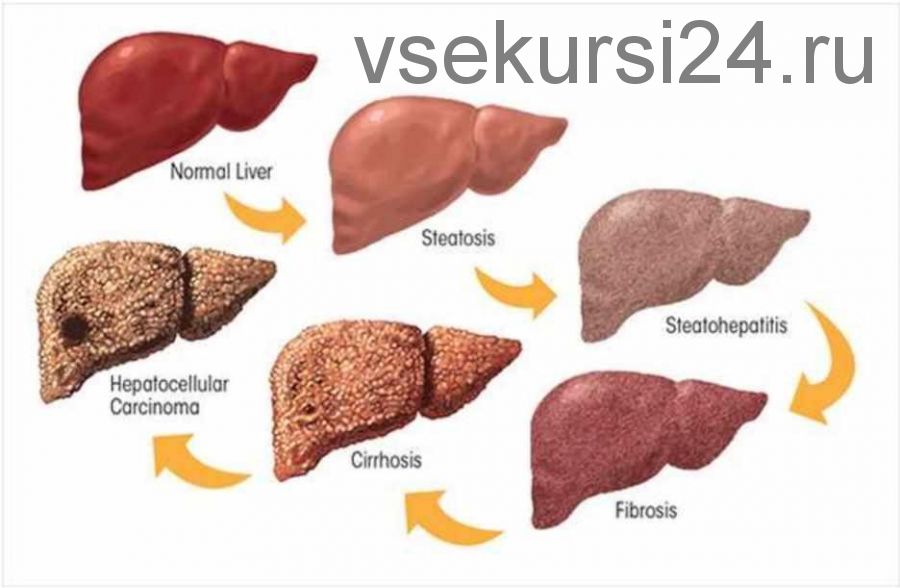

Изображения заболеваний печени: признаки и симптомы